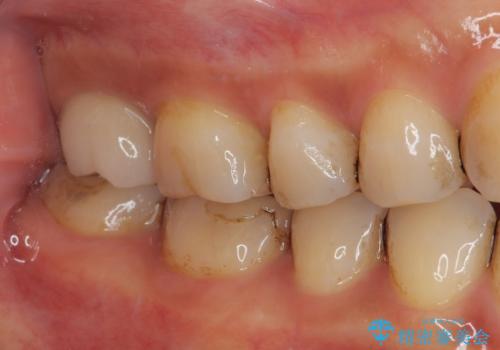

被せものが欠けた オールセラミッククラウン

- 奥歯の被せものが欠けたとのことで来院された患者様です。上の奥歯なので機能面や強度を優先しPGAクラウン(ゴールドクラウン)のご提案をしましたが、セラミックの被せものがよいとのことでオールセラミッククラウンによる補綴治療を行っていくことにしました。

拡大鏡視野下で古い被せものを除去し、オールセラミッククラウンに適した形に整えました。

患者さまにはオールセラミッククラウンの色味、機能面共に満足していただけました。

今後はナイトガードを使用してもらいながら、メインテナンスで通っていただく予定です